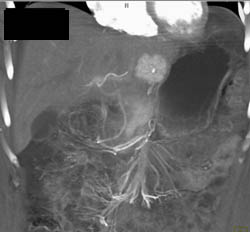

Focal Nodular Hyperplasia (FNH)